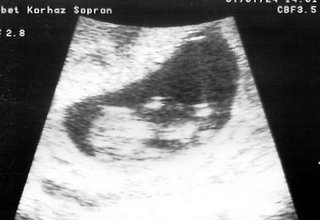

Megvolt az UH!!!! Minden okééééééééééé!!!!Adatok: CRL: 41 mm, petezsák: 60 mm, fejecske: 16 mm, nyaki redő 1 mm, két kéz, két láb, orrcsont oké. És nagyon mozgékony!

Nem tudom mennyi fog látszani a képből, próbáltam rajta finomítani scannelés után, nem tudom mennyire sikerült. A bal oldalon van a kis buksija:-) Jó bogarászást! :D

Kata Kép 12 hetes UH